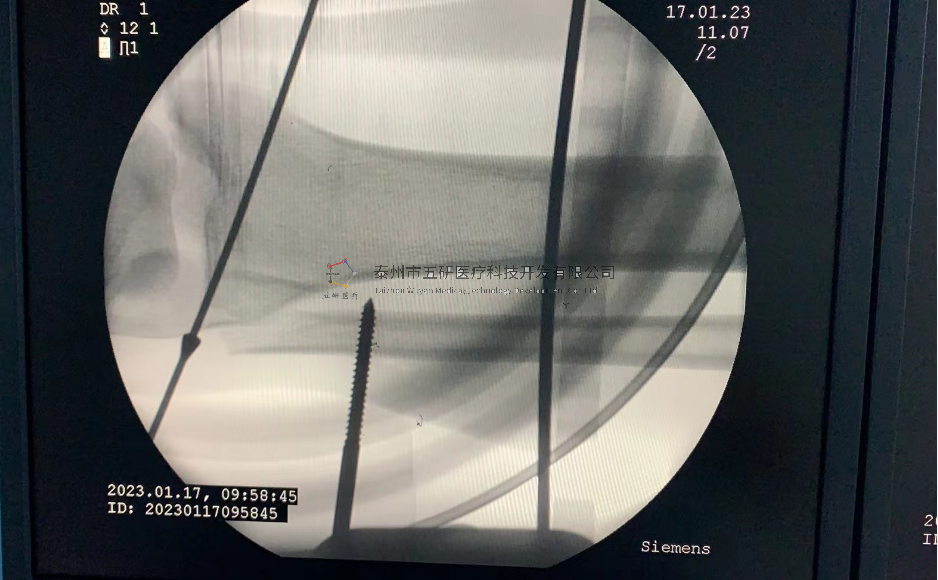

【手術(shù)資料】

【患者情況】脛骨遠(yuǎn)端骨折伴腓骨骨折

【影像圖片—術(shù)前】

【影像圖片—術(shù)后】